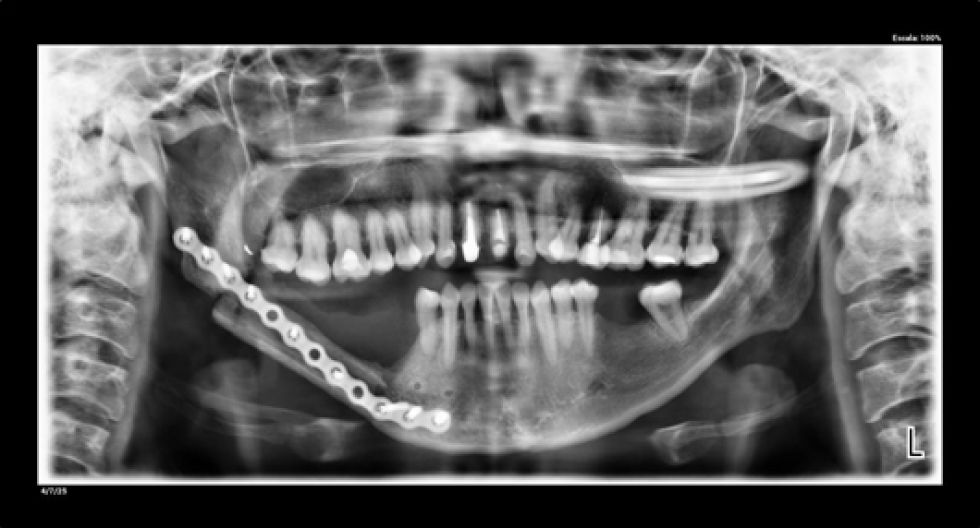

Radiografías panorámicas de control luego de la cirugía microvascularizada. La pieza está unida por una placa sobre el hueso del peroné microvascularizado (4 de julio de 2025).

Radiografías panorámicas de control luego de la cirugía microvascularizada. La pieza está unida por una placa sobre el hueso del peroné microvascularizado (4 de julio de 2025). Foto: Cedida